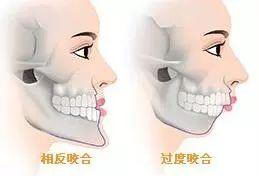

并且可能伴随着咬合不正(位置不对)的情况,此时需要采取的是复杂的双鄂手术,上颚(上颌骨)和下颚(下颌骨)同时截断,重新矫正到理想的位置上,从而使患者拥有正确的咬合状态和脸型。

除了能改善双鄂突出导致的凸嘴以外,撅下巴(地包天)、长脸、面部不对称、咬合不正等也是在治疗的范围之内的。

▲双鄂手术可以改善咬合不正

手术的目的不仅仅是将凸出的嘴向后推几毫米, 让脸变得自然,美丽,此外也是可以矫正牙齿咬合不正,让咀嚼、发音、吞咽功能恢复正常。